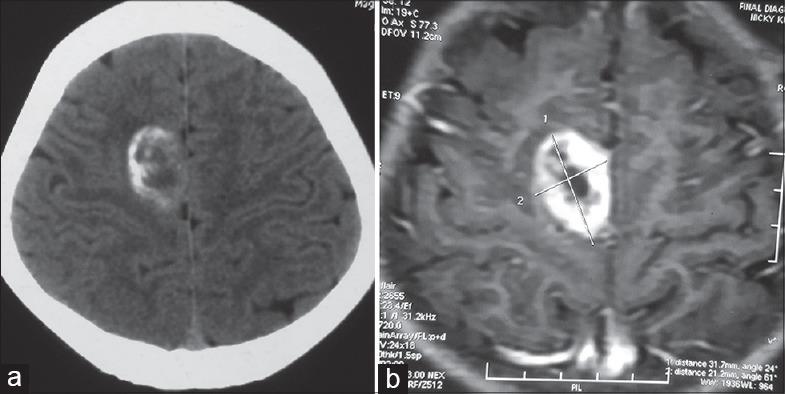

Ependymoma tends to occur commonly along either on ventricular surfaces of the brain or central canal of the spinal cord. Rarely, ependymoma can develop in the cerebral cortex without attachment to the ventricular structures. However, such occurrence in the purely extra-axial compartment in the falcine region mimicking falcine meningioma is exceedingly rare. The detailed search of primary falcine ependymoma (PEFE) in Medline and PubMed yielded only five isolated case reports. All cases occurred in patient older than 17 years of age; however, our case was a 9-year-old girl. PEFE tends to occur more commonly in male with a male to female ratio of 3:2, with the mean age of 28.8 years (range 17-43 years), lesion had intra-operatively had solid consistency in all cases. All cases were subjected to surgical resection followed by adjuvant radiotherapy; however, in addition, one case also received chemotherapy, with an average follow-up period of 9 months, however, missing in one case. The mean size of the tumor was 5.25 cm (range 1.8-7.2 cm). The authors present a unique case of PEFE in a 9-year-old girl with 8.6 cm ×6 cm ×5.4 cm-sized giant primary falcine ependymoma, managed surgically successfully. To the best of the authors' knowledge, the current case is the first case of pediatric extra-axial falcine ependymoma occurring within the first decade of life in the western literature, showing rapid evolution over 1½ month's period into a giant size. Brief pathogenesis, clinical feature, and management along with the pertinent literature are reviewed briefly.

摘要

室管膜瘤通常易于发生在脑室内表面或脊髓中央管。罕见的是,室管膜瘤可在大脑皮质中发生而不附着于脑室结构。然而,在镰状区域的纯轴外间隙中发生这种类似镰状脑膜瘤的情况极为罕见。在医学文献数据库(Medline)和医学期刊数据库(PubMed)中详细检索原发性镰状室管膜瘤(PEFE)仅得到5例孤立的病例报告。所有病例均发生在17岁以上的患者中;然而,我们的病例是一名9岁女孩。PEFE在男性中更常见,男女比例为3:2,平均年龄为28.8岁(范围17 - 43岁),所有病例术中病变质地均为实性。所有病例均接受了手术切除,随后进行辅助放疗;然而,此外,1例还接受了化疗,平均随访期为9个月,但有1例失访。肿瘤的平均大小为5.25厘米(范围1.8 - 7.2厘米)。作者报告了一例独特的PEFE病例,患者为一名9岁女孩,患有大小为8.6厘米×6厘米×5.4厘米的巨大原发性镰状室管膜瘤,手术治疗成功。据作者所知,目前该病例是西方文献中首例发生在生命第一个十年内的小儿轴外镰状室管膜瘤,在1个半月的时间内迅速发展为巨大肿瘤。本文简要回顾了其简要发病机制、临床特征、治疗方法以及相关文献。